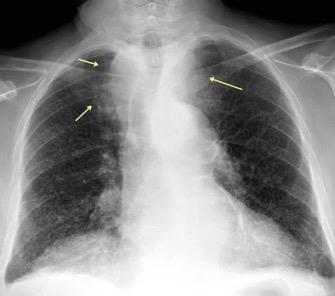

Triada de Garland

Ganglios paratraqueales derechos e hiliares bilaterales

95% de pacientes tienen ganglios hiliares bilaterales aislados o con afectación mediastínica (espec. paratraqueal derecho).

Criado E et al. Pulmonary sarcoidosis: typical and atypical manifestations at high-resolution CT with pathologic correlation. Radiographics. 2010